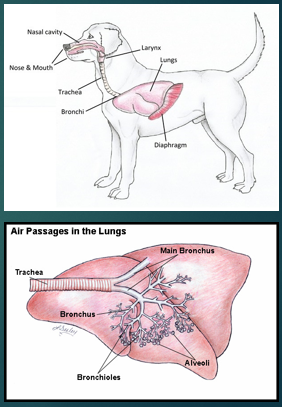

Lower respiratory tract

Trachea

Bronchi

Bronchioles

Lung Parenchyma - Interstitial and alveolar spaces